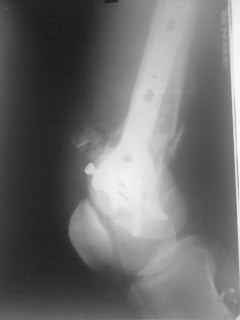

Уважаемые коллеги, прооперирована пациентка антеградным штифтом Остеомед, костная пластика не проводилась. Выбранный штифт по каналу бедренной кости на фоне отсутствия переднего кортикала в канале не центрируется. Технически неприятно, отсутствие передней и внутреннебоковой стенки до зоны мыщелков сильно затрудняло репозицию. Получилась вот такая картина. После стабилизации - очевидное повреждение ПКС и боковая нестабильность. В общем и далее будет чем заняться. Нам и в дальнейшем будет очень интересно мнение коллег.

|

НО> пластика не проводилась. Выбранный штифт по каналу бедренной кости на фоне отсутствия

НО> переднего кортикала в канале не центрируется.

Можно создать искусственную стенку из спиц или винта.

НО> Получилась вот акая картина.

Молодцы, здорово получилось. Как ввдили самый дистальный винт? Надколенник не мешал?